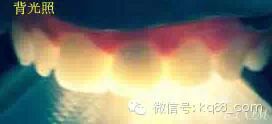

檢查:明顯可見22牙冠橫向斷裂至頸1/3處,近遠中與腭側斷裂至齦下??梢?/span>11牙冠斜向近中斷裂,近中與腭側均斷裂至齦下。21牙冠中1/3有裂痕。11 21 22松動(0),11 21叩(+),22叩(-),11 21 22探(-),11 21 22冷熱(-)。11 21 22唇側牙齦與粘膜和根尖相應部位未見明顯改變。11 22腭側牙齦增生性改變。11 21 22腭側粘膜和根尖相應部位未見改變。11 21 22舌側窩均有充填物。面部左右對稱無改變。余牙正常。(11,21,22牙冠顏色無改變)。 輔助檢查:X線片檢查11 22牙冠均有缺失。11 21 22 髓腔內均有充填物,11充填不到位, 21充填不實,22充填到位髓腔高密度影像。11 21 牙周膜有增寬,21根尖區(qū)有2mm左右低密度影像。未發(fā)現(xiàn)有牙根側穿或斷裂異物。 診斷:11,21慢性尖周炎,11,22殘冠。 治療計劃: 22無需治療。11 21 建議牙齒根管再治療。告知情況及費用。 1,11 21去除根充物。 2,11 21根管治療。 3,11 22纖維樁樹脂核修復。 4,高頻電刀去除11 22腭側牙齦組織到斷面。 5,11,21,22全瓷單冠修復牙齒。 治療過程:經(jīng)患者同意。H銼去除11 21原有充填物,未發(fā)現(xiàn)明顯滲出物,無異味。K銼疏通根管,VDW根測儀測量長度,11牙20mmWL,21牙20mmWL。S3鎳鈦器械預備根管。(全程1%次氯酸鈉沖洗EDTA溶解潤滑)試尖片顯示牙膠未到位,繼續(xù)向牙根尖各2mm進入預備。吸潮紙尖吸干根管,登士柏樹脂根充糊劑輸送至根尖部位,以測量數(shù)據(jù)用牙膠尖冷充側壓充填根管,3M玻璃離子封閉根管口。不可用患牙啃咬硬物,擇日冠修復。 輔助檢查:插針X線片顯示根管內充填物已經(jīng)取出。試尖片顯示牙膠尖未到位,繼續(xù)用K銼和機括向根尖預備。根充結束片顯示根充密實,無超充,無欠充。 醫(yī)囑:常規(guī)醫(yī)囑,不適隨診。 各步驟操作見下圖 于洪濤 2015.02.03 復 診 主訴:無疼痛,不適癥狀已經(jīng)消失。 檢查:11 21 充填物存在邊緣封閉完好,叩(-)松動(0)牙齦及周圍同初診。11 21 22無任何不適。 治療過程:由于患者自身原因即將兩個月來復診。拍X線片,去除11 22髓腔內部分牙膠,P鉆預備根管到達預定位置。粘結纖維樁,制作冠核。初預備11 21 22牙冠。高頻電刀按廠家要求功率和方法去除11 22腭側牙齦組織到達牙齒斷裂部位,調整檔位和功率繼續(xù)凝固和精修腭側組織,11 21 22排齦精修拋光。硅橡膠兩次法取模,可見模型完整肩臺清晰。制作臨時冠,科爾不含丁香油臨時冠粘結系統(tǒng)粘接。 模型送技師制作。預約義齒佩戴時間。(需術前牙齒比色) 輔助檢查:X線片顯示根尖低密度影像消失,牙周未見異常。X線片顯示纖維樁密合到位。 醫(yī)囑:不可用臨時牙肯咬硬物,不適隨診。 各步驟操作見下圖 于洪濤 2015.03.26 復 診 主訴:牙齒無癥狀,自感腭側術區(qū)舌舔粘膜不適。 檢查:臨時冠完整,無松動,邊緣緊密。牙齒無疼痛,唇側牙齦無明顯紅腫,腭側牙齦愈合良好,牙冠肩臺邊緣清晰。腭側牙齦術區(qū)中度觸及有少量滲血。 治療過程:義齒制作完成。去除臨時冠及粘結物。義齒試戴調整完全就位,無懸突,無縫隙。清洗義齒,氫氟酸處理義齒50秒(加強醫(yī)患防護),沖洗吹干,偶聯(lián)劑處理備用。基牙37%酸處理15秒,沖洗吹干,隔濕,排齦,涂第五代粘結劑。小蜜蜂雙固化樹脂水門汀激活攪拌注入義齒中,按順序就位,加壓力,牙線去除牙縫隙多余樹脂,涂阻氧劑,基牙唇腭側各光照固化3秒之后去除多余水門汀取出排齦線,繼續(xù)光照固化牙齒每個面20秒。精細查找去除多余水門汀。 醫(yī)囑:1,患牙咀嚼硬物加以注意。 2,常規(guī)醫(yī)囑,不適隨診,。 3,加強口腔衛(wèi)生意識。定期復診檢查。 各步驟操作見下圖 于洪濤 2015.04.07 回訪病例 主訴:咀嚼食物非常自如,無任何不適。 檢查:義齒牙體完整。無松動,無叩痛。唇側牙齦紅潤質韌無萎縮,腭側術區(qū)牙齦愈合良好,無炎癥改變。唇腭側根尖相應部組織無改變。余牙正常。 輔助檢查:X線片顯示牙根及周圍未見異常。未見骨萎縮。牙冠及頸部未見異常。 醫(yī)囑:定期檢查義齒,不適隨診。 各步驟操作見下圖 于洪濤2015.04.28